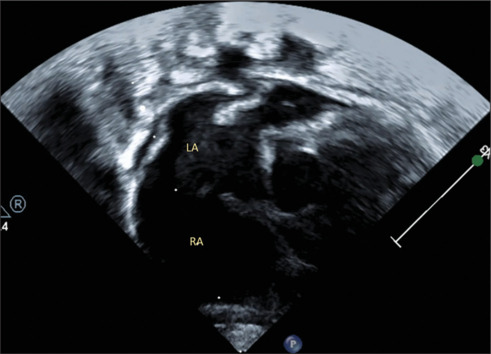

Truncus arteriosus (TA) is a major cyanotic heart malformation infrequently associated with aortic arch interruption and isolation of the branch pulmonary artery. Anomalous superior vena caval drainage to the left atrium (LA) is hitherto unreported in TA. In a 45-day-old infant diagnosed with TA and cyanosis, anomalous drainage of the right superior vena cava into the LA was not identified preoperatively or intraoperatively. It was detected postoperatively due to persistent hypoxemia. The anomaly posed unique challenges in the subsequent management. This case report highlights the unusual association of systemic venous drainage in TA.